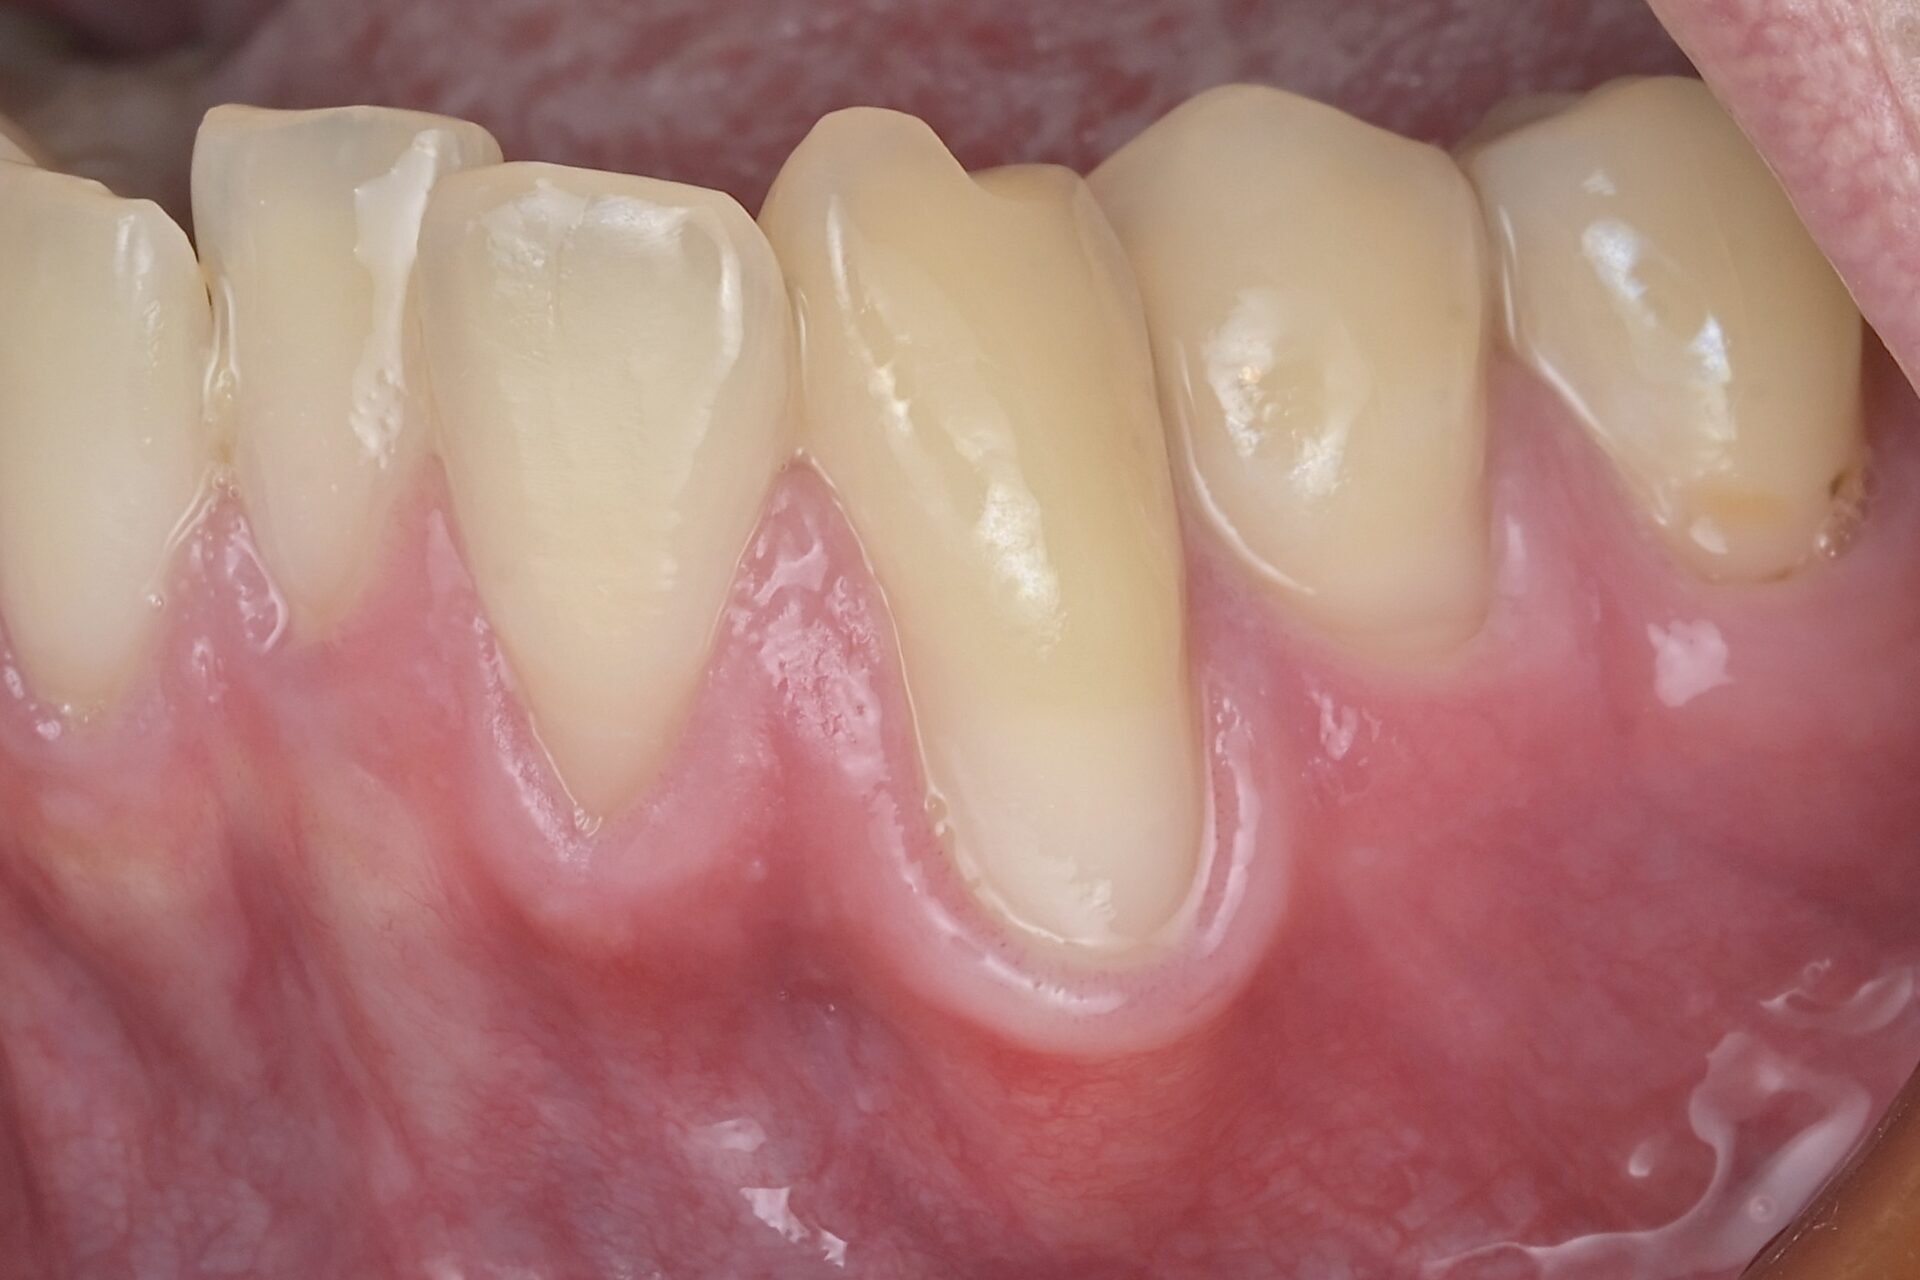

術後(SATT)

根面に歯周組織再生能力のあるエムドゲインを塗ります。その後に口蓋部から結合組織を採取して露出根面に吸収性の糸で縫い付けます。今回はSATTという切開縫合の術式を用いました。 -